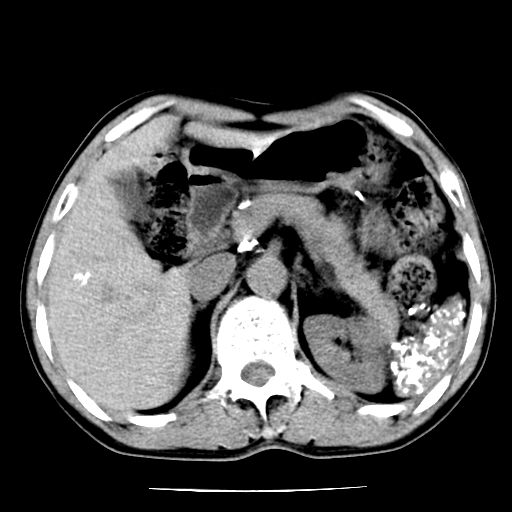

男,59岁,“结核性胸膜炎”30余年,胸部经常疼痛,多次x检查提示“肺部”炎症。腹部疼痛5日,b超提示:“肝内短管结石,余显示不清,建议进一步检查。”

两肺结核并右侧胸腔积液;脾脏、腹腔及腹膜后淋巴结结核[陈旧性];肝内胆管结石

胸部腹部都是结核(双肺。纵隔淋巴结,肝脏,脾脏,肠系膜)

一元论——结核。